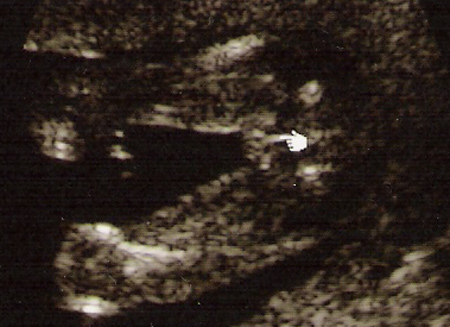

İşte karşınızda, kızımızın kız olduğunu anlamamıza yarayan ultrason görüntüsü. “Ben bir şey görmüyorum!” diyor olabilirsiniz. Kadın doğumcu veyahut çok yakın zamanda çocuk sahibi olmuş bir kişi değilseniz çok normal, biraz yardım şart:

– Velede şu anda alttan bakıyorsunuz.

– Solda en altta gördüğünüzkendisinin bir bacağı, dolayısıyla biraz yukarısında da diğer bacak var.

– Bu durumda fotografın sağ tarafı kendisinin poposu.

– Doktorumuzun (sağolsun) imleçle işaret ettiği yerde bir şey görülememesinin sebebi de, baktığınız kişinin bir “kız” olması :)

Hala ikna olmayan varsa, yapacak bir şey yok, hep beraber Temmuz ortasına kadar bekleyebiliriz ancak…